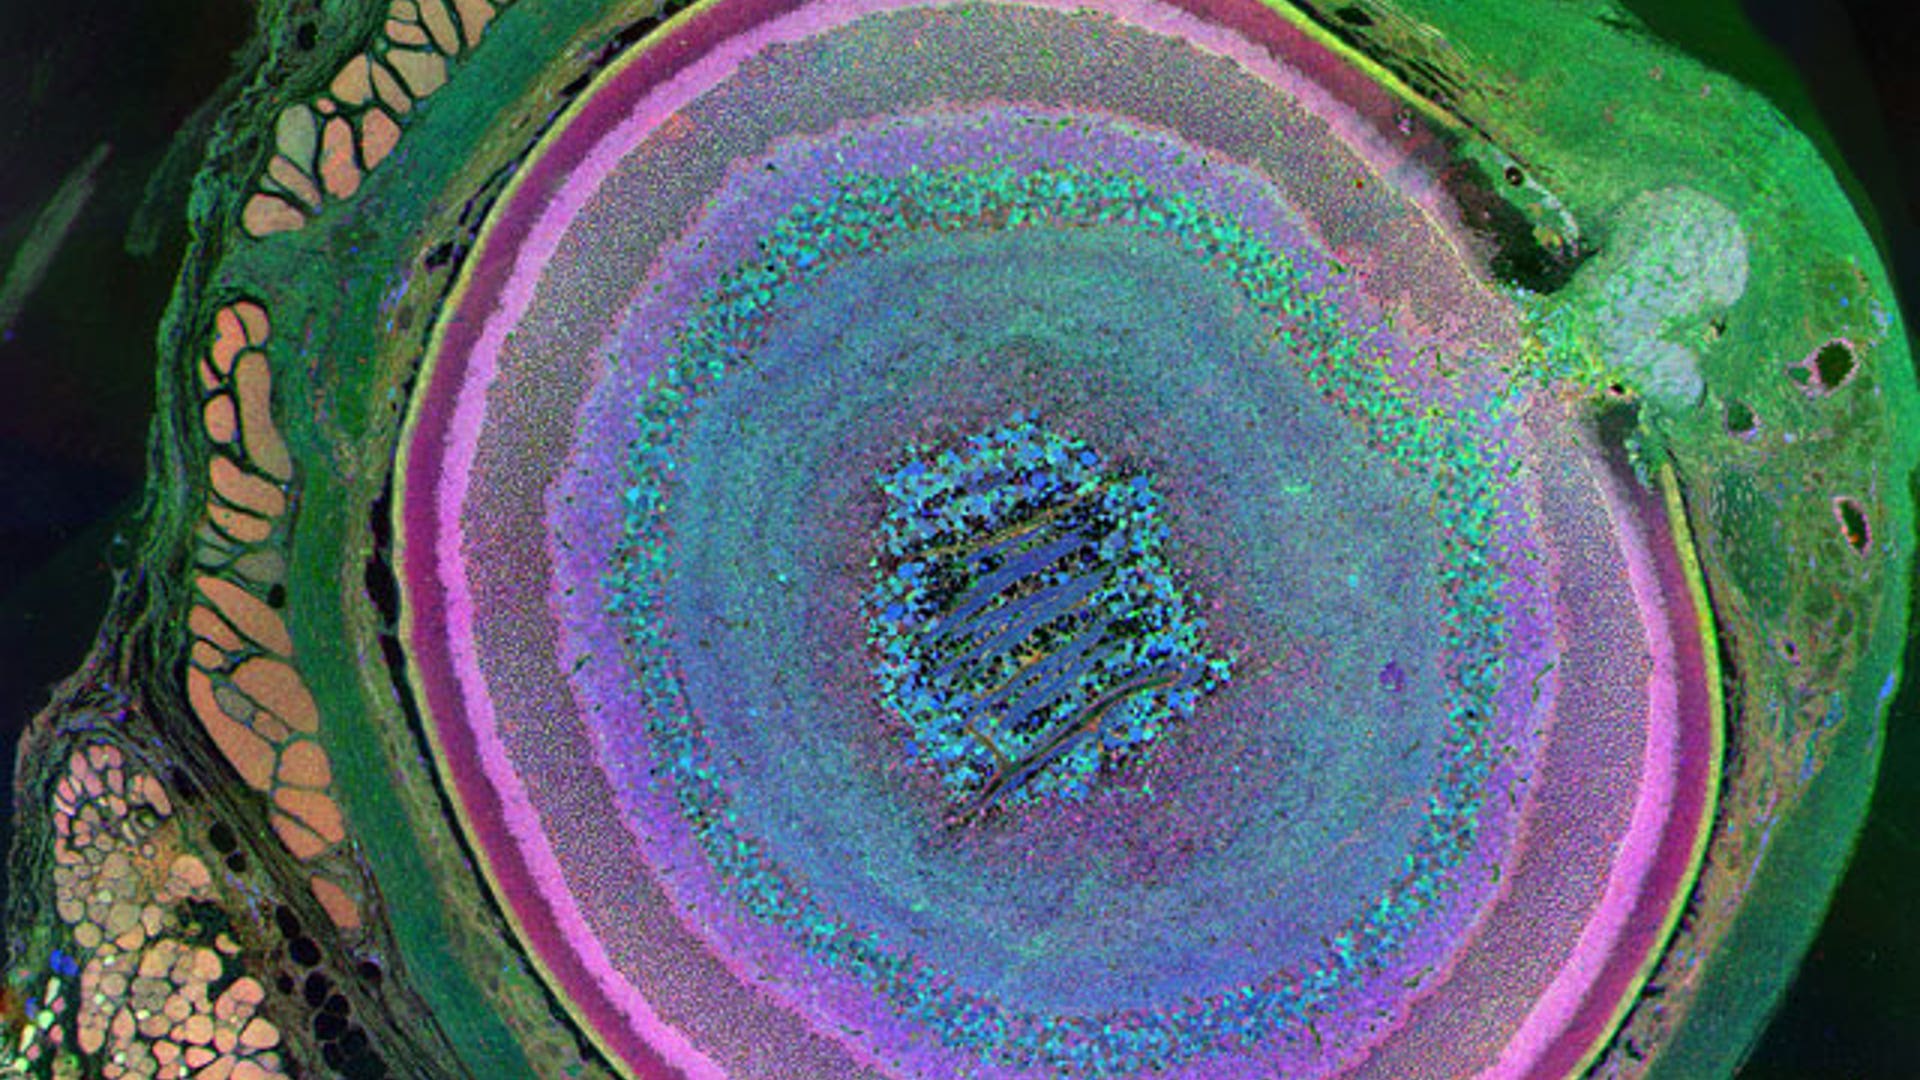

Photography (Winner) This beautiful set of concentric rings and shapes is actually a metabolic look at the wide diversity of cells in the eye of a mouse. In all, 70 different types of cells are depicted, from muscles to retina, each colored a unique shade. Muscle cells, located at the left edge of the image, look pale yellow, whereas scleral tissue, surrounding the entire orb, shows up green in this image.read moreBryan William Jones, The University of Utah, Moran Eye CenterShare![Microscopic Image of Trichomes on the Skin of an Immature Cucumber]()